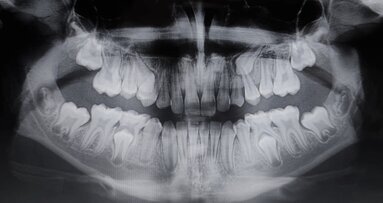

G. I. paziente di anni 50, si presenta alla nostra osservazione con una frattura longitudinale della radice dell’elemento 4.5 dovuta a infiltrazione cariosa della vecchia corona protesica. Questa situazione ha provocato nell’osso alveolare del paziente una grossa lesione che è andata ad interessare anche la corticale vestibolare. Per poter sostituire la radice con un impianto sarebbe necessario un intervento di chirurgia ossea rigenerativa ma un’alternativa meno invasiva è la rigenerazione del tessuto osseo ottenuta tramite l’estrusione forzata dell’elemento che rigenera osso durante la sua lenta migrazione grazie al legamento parodontale. In accordo con il paziente, dopo opportuna spiegazione dei benefici e dei tempi dell’approccio con estrusione ortodontica, si decide di procedere con questo iter evitando così l’intervento di rigenerativa.

L’estrusione completa del frammento ha richiesto un tempo di 6 mesi, durante i quali è stata modificata più volte l’inclinazione della molla per evitare che il movimento diventasse ortogonale al segmento e mantenere la traiettoria prevista. Così facendo, è stato possibile rigenerare naturalmente l’intero alveolo e inserire, dopo 3 mesi di ulteriore maturazione del tessuto, in un contesto osseo ideale e perfettamente rigenerato un impianto Syra (Sweden & Martina) di diametro 4.25 mm e lungo 11 mm.